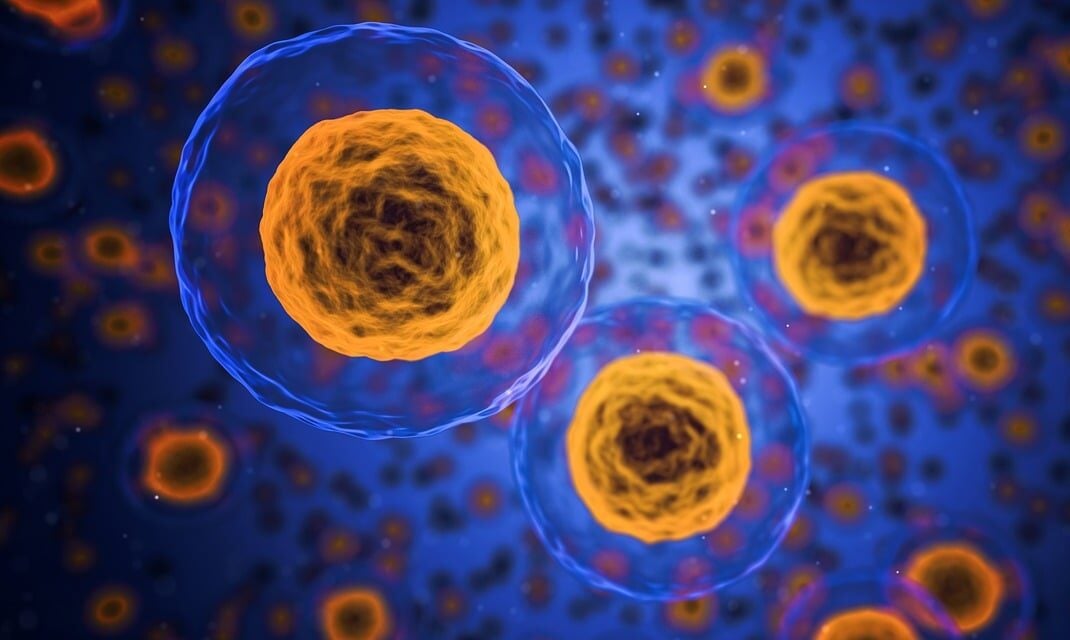

Nanoparticle-based targeted delivery unleashes the full power of anti-cancer drugs

A new paper in Cell Reports Medicine details the development of a nanoparticle-based system that delivers concentrated chemotherapy specifically to cancer cells and not normal cells, potentially allowing clinicians to administer higher, more effective …